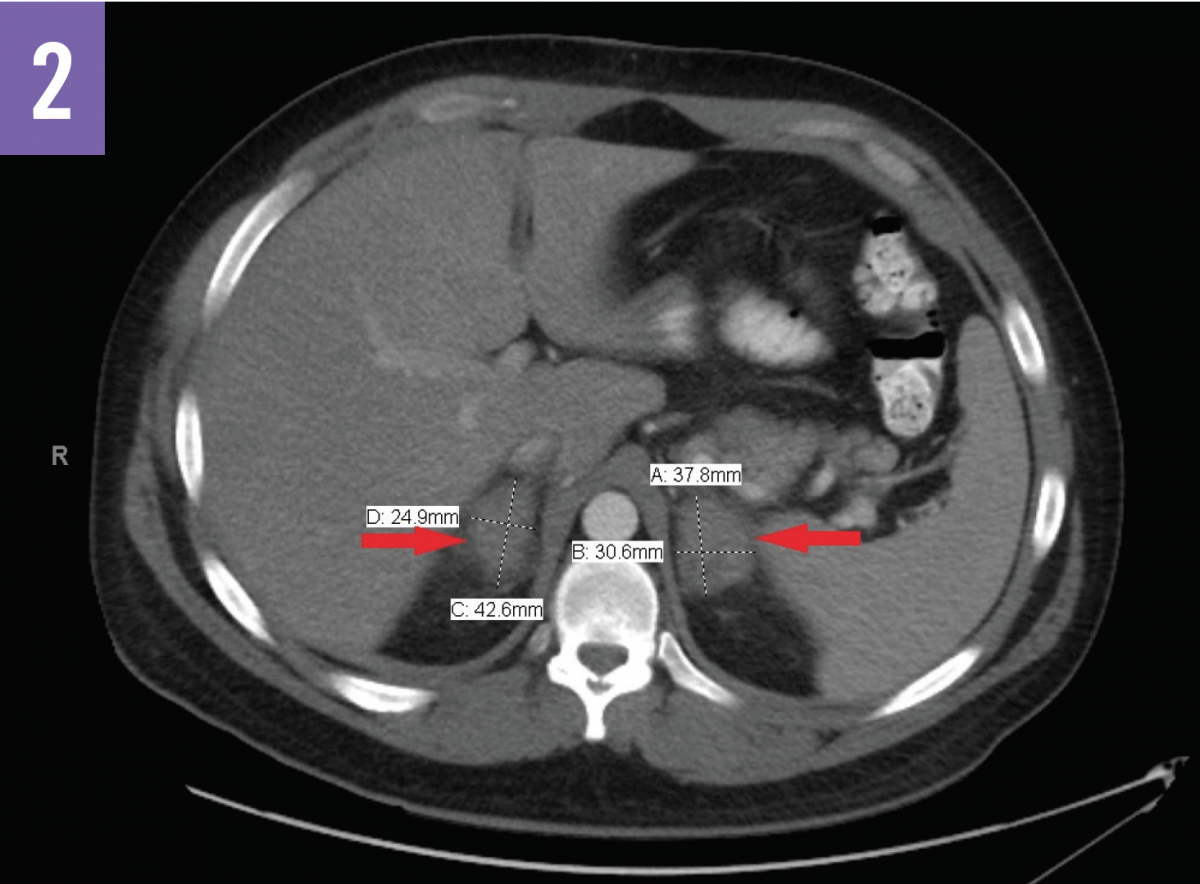

Computed tomography (CT) scans of the abdomen (Figures 1 and 2) showed acute bilateral adrenal gland enlargement. Compared with abdominal CT scans done 10 days prior for acute cholecystitis, these findings were new and highly suggestive of acute bilateral adrenal hemorrhage. His serum cortisol level was found to be <0.16 µg/dL (reference range, 5-25 µg/dL). The patient remained hemodynamically stable. Results of repeated laboratory tests for APLS, including anticardiolipin antibody and lupus anticoagulant testing, were positive for APLS.